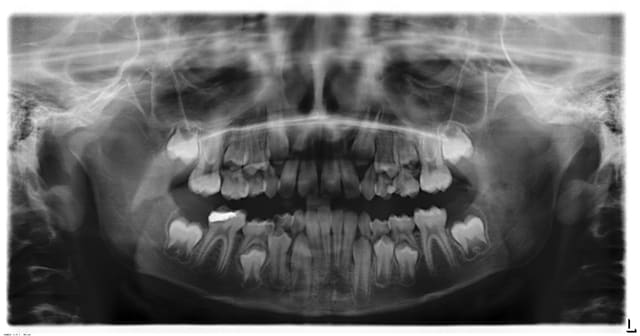

Garçon de 8 ans avec une carie profonde sur 46.

La dent est sensible chaud/froid, l'enfant prend régulièrement des antalgiques.

Quelle est la conduite à tenir?

Pour moi et je peux me tromper ça sent la pulpec + apexification (la carie a atteint la pulpe sur la radio qui est donc infectée...ça sent assez mauvais).

Quelques photos ci-dessous d'un cas similaire au tien.

Si la symptomatologie et/ou l'effraction sont importants, fais une pulpotomie au MTA (propre, éviction pulpe camérale avec une fraise boule stérile qui n'a rien touché, sous digue).

Si après éviction de la pulpe camérale et hémostase, tu observes des moignons radiculaires inflammatoires (saignement abondant qui ne s'arrête pas), tu devra probablement passer à l'apexification.